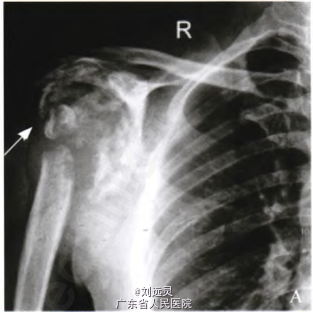

男,43岁,以右肩病变入院。10年前依据症状及颈部MRJ诊断为C1~C6水平脊髓空洞症,后根据病史、X线及穿刺活检在外院诊断为Charcot关节病(Charcot’s anhrosis,CA)。

体格检查:右肩关节肿胀、活动无受限,无红肿,皮温不高,压痛不明显,触及大小约12 cm×10 cm×10 cm囊性肿块,质软,有波动感。右上肢肌力正常,右肩关节及右侧胸部触觉及痛觉降低,上肢肌肉和大鱼际肌较对侧萎缩。